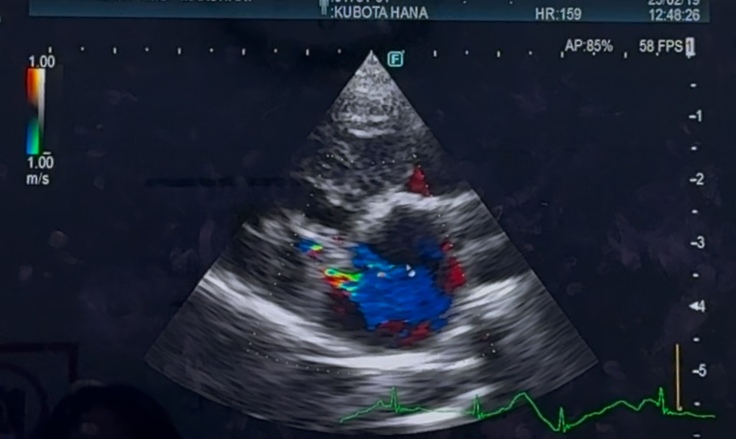

心臓手術後 1年半検診でした

心臓手術後、1年半検診でした

華の心臓は、術前、術後で

大きさはあまり変わっておらず

左心房の大きさは

今も、正常の倍はあり

逆流も、少し残っており…

右心の三尖弁逆流もあります

抗血栓薬を、今も飲み続けています

検査結果も、良くも悪くも…

現状維持でしたε-(´∀`;)ホッ